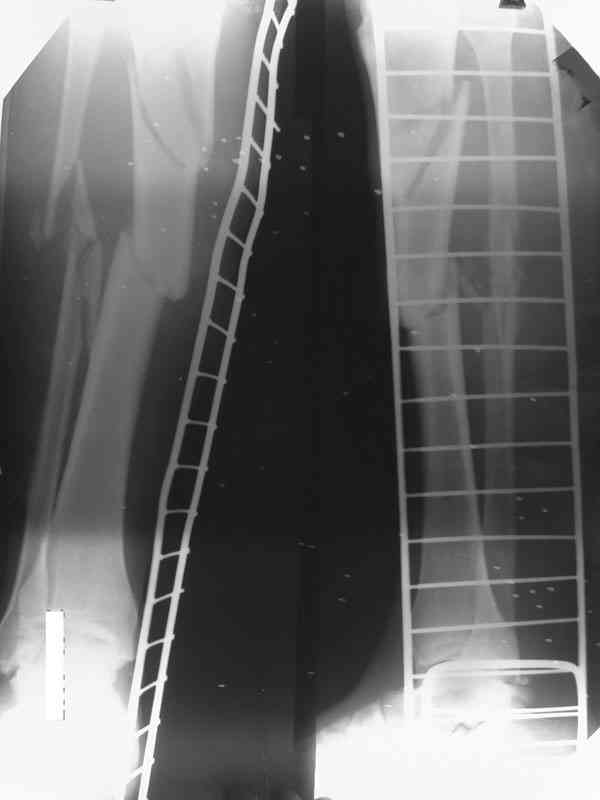

А доклад из Германии, действительно, был интересный. Правда пока у авторов немного наблюдений. И еще прозвучала мысль, этот метод не предназначен для применения при наличии проявлений инфекции. Прилагаю несколько иллюстраций (1 - вид кейджа во время операции перед закрытием лоскутом на свободной ножке, 2 - рентгенограммы через 32 месяца после операции, 3 - слайд, перечисляющий преимущества методики).